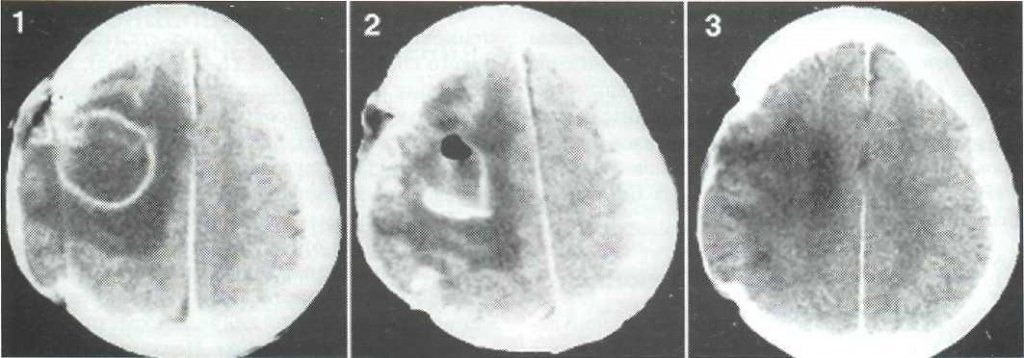

- 1 стадия (1-3 дня) наблюдается энцефалит – это начальное воспаление мозга. Самый легкий период, болезнь поддается излечению благодаря антибактериальной терапии или проходит самостоятельно путем рубцевания.

- 2 стадия (4-9 дней). В абсцессе уже образовался гнойник, который с каждым днем увеличивается в объёмах, если не обращаться к медикам.

- 3 стадия (10-13 дней). Вокруг гнойной полости образуется защитная пленка, которая не дает образованию распространяться дальше.

- 4 стадия (3 неделя). Пленка полноценно уплотнилась. В некоторых случаях начинается регресс болезни или вокруг капсулы образовываются новые очаги заражения.

Дальше это только подготовка к хирургическому вмешательству. Врачи клиник на данный момент практикуют полное удаление абсцесса или его дренирование. Пунктуационная аспирация применяется на ранних стадиях или на этапе церебрита.

Её эффективность доказана в случаях, когда гнойник расположен глубоко в голове. Если неврология больного покажет наличие воздуха в абсцессе или ухудшение общего состояния пациента – новообразование нужно удалять.